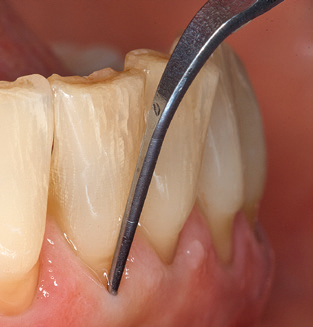

Das aktuelle Arbeitskonzept für die UPT

Die Aktualisierung der Anamnese stellt im Rahmen der UPT eine zentrale Maßnahme dar, sie sollte mindestens einmal jährlich erfolgen. Sie dient dazu, mögliche neue Risikofaktoren zu erkennen und zu dokumentieren. Vor allem dann, wenn ein Patient langjährig betreut wird, ist es wichtig, zu erfahren, ob sich patientenspezifische und allgemeinmedizinische Risikofaktoren verändert haben. Hier sollte an erster Stelle an ein erhöhtes Risiko durch Diabetes gedacht werden, aber auch andere allgemeinmedizinische Erkrankungen (kardiovaskuläre Erkrankungen und Neoplasien) können aufgrund der erfolgten Therapien und der notwendigen Medikamenteneinnahme zu einem veränderten Risikoprofil führen. Das Update der Anamnese ist also auch im Rahmen der UPT sehr wichtig, um gegebenenfalls aufgrund eines veränderten Risikoprofils eine Veränderung des Behandlungsintervalls zu veranlassen. Im nächsten Schritt ist es wichtig, der Diagnostik besondere Aufmerksamkeit zu schenken. Die Instrumentation ist zwar ein zentraler Bestandteil der UPT, in keinem Fall sollte sie aber Bestandsaufnahme und Dokumentation verdrängen. Für die Diagnose ist dabei der parodontale Befund unerlässlich, eine Zunahme der Sondierungstiefen und eine Erhöhung des BOPIndex sind zentrale Indikatoren für eine Progression parodontaler und periimplantärer Erkrankungen. Zum Erheben der benötigten Daten darf daher nicht davor zurückgeschreckt werden, auch Implantate zu sondieren. Dabei ist es wichtig, dass hierfür millimeterskalierte PARSonden verwendet werden. Für die Sondierungsbefunde an natürlichen Zähnen haben sich seit Jahrzehnten metallische Sonden bewährt. Bei Implantaten ist die Herausforderung für das Erheben korrekter und reproduzierbarer Sondierungsbefunde größer. Da es durch die Diskrepanz von Implantatdurchmesser und Kontur der Suprakonstruktion regelmäßig zu einer Überkonturierung der Suprastruktur kommt, sind für Sondierungen an Implantaten flexible, aber dennoch millimeterskalierte Son den sehr sinnvoll (z. B. Colorvue Kit PCV11KIT6, HuFriedy; Abb. 4).